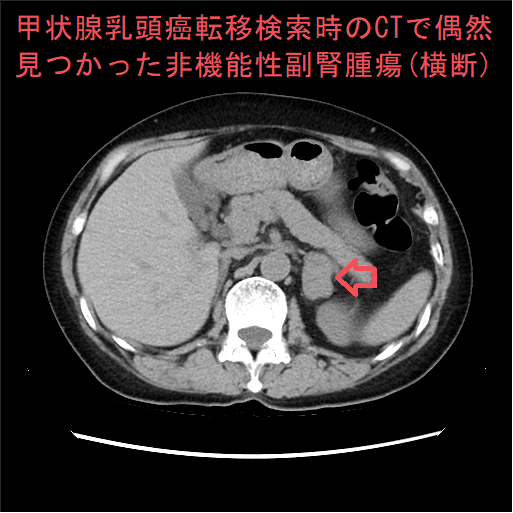

副腎は左右腎臓の上にあるのホルモン分泌臓器。副腎腫瘍はホルモンを作る機能性副腎腫瘍と作らない非ホルモン産生性腫瘍がある。腹部超音波検査やCTで偶然(1-5%、高齢者は10%)副腎腫瘍が発見される(副腎偶発腫瘍:インシデンタローマ)。約75%は副腎腺腫、約50%は非機能性副腎腺腫だが3cm以上なら副腎癌(副腎原発1%/転移性5%)の事がある。骨髄脂肪腫3%。機能性副腎腫瘍はクッシング症候群10%・褐色細胞腫10%・原発性アルドステロン症5%。単純CTでCT値が10HU未満の低吸収値になる副腎腫瘍は脂質を多く含む副腎腺腫。

腹部超音波検査やCTで偶然(1-5%、高齢者では10%)副腎腫瘍を発見される事があり、副腎偶発腫瘍(インシデンタローマ)と呼ばれます。

大阪大学の報告では、副腎偶発腫瘍(インシデンタローマ)の大半(77.0%)はCTで発見され、残りは腹部超音波検査(14.6%)、MRI(4.2%)、PET検査(4.2%)で同定。右側よりも左側に多く、腫瘍の平均直径は21±11mm。73.3%はホルモンを作らない非機能性副腎腫瘍。機能している腫瘍を有する患者は、機能していない腫瘍を有する患者よりも有意に若く、腫瘍の直径が大きかった。

非機能性副腎皮質腺腫が3cm以上の場合、副腎癌(副腎原発1%/転移性5%)の事があります。